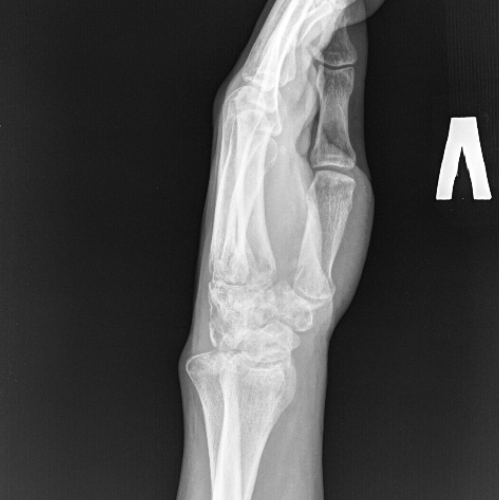

The examination revealed chronic transscaphoid perilunate dislocation of the left hand, arthrosis, synovitis of the left wrist joint, and a nonunion of a comminuted fracture of the styloid process of the left ulna (Fig. 3–4).

| Fig. 3 Radiographs at admission | |